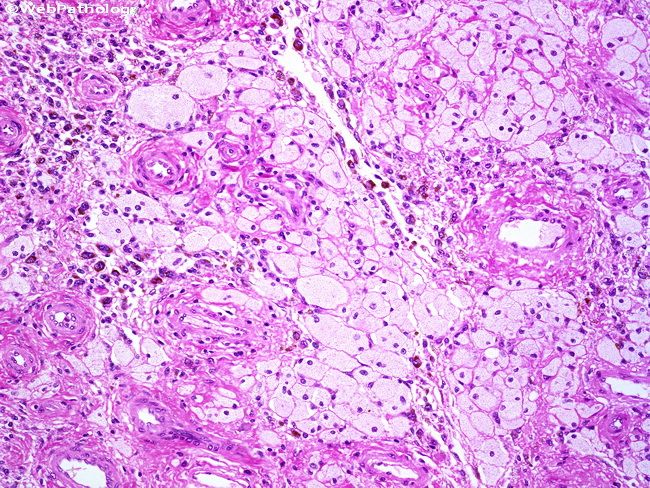

Пигментный виллонодулярный

Пигментный виллонодулярный 113 фотографий